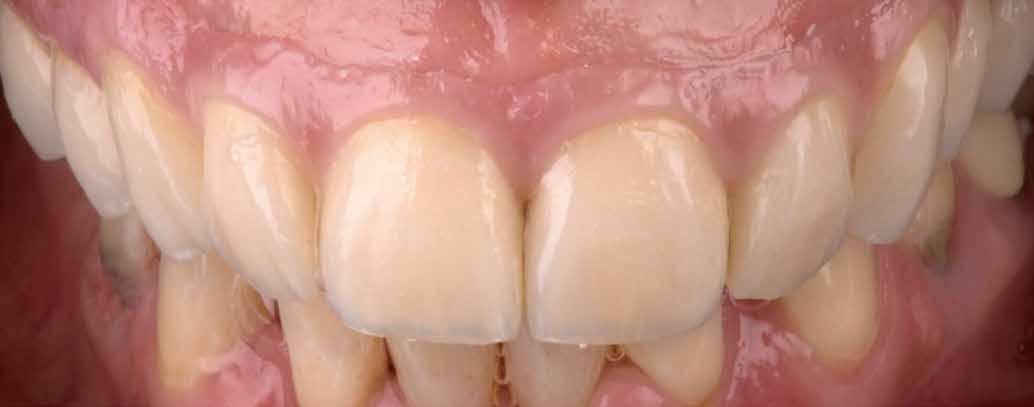

Amint megérkezett a végleges pótlás a laboratóriumból a rendelőbe, a stégek felkerültek az implantátumokra (72–73. képek). Ketac Zem-mel ragasztották be őket. Ezt követően kerültek szájba a kivehető fogsorok, még egyszer optikailag ellenőrizve a korrekt illeszkedést. Jó látni, milyen harmonikusan illeszkedik a természetes környezetbe minden. A front optimalizált esztétikája is jól érvényesül (74–81. képek). A tökéletes illeszkedést végül röntgenképpel is ellenőrizték (82.kép).